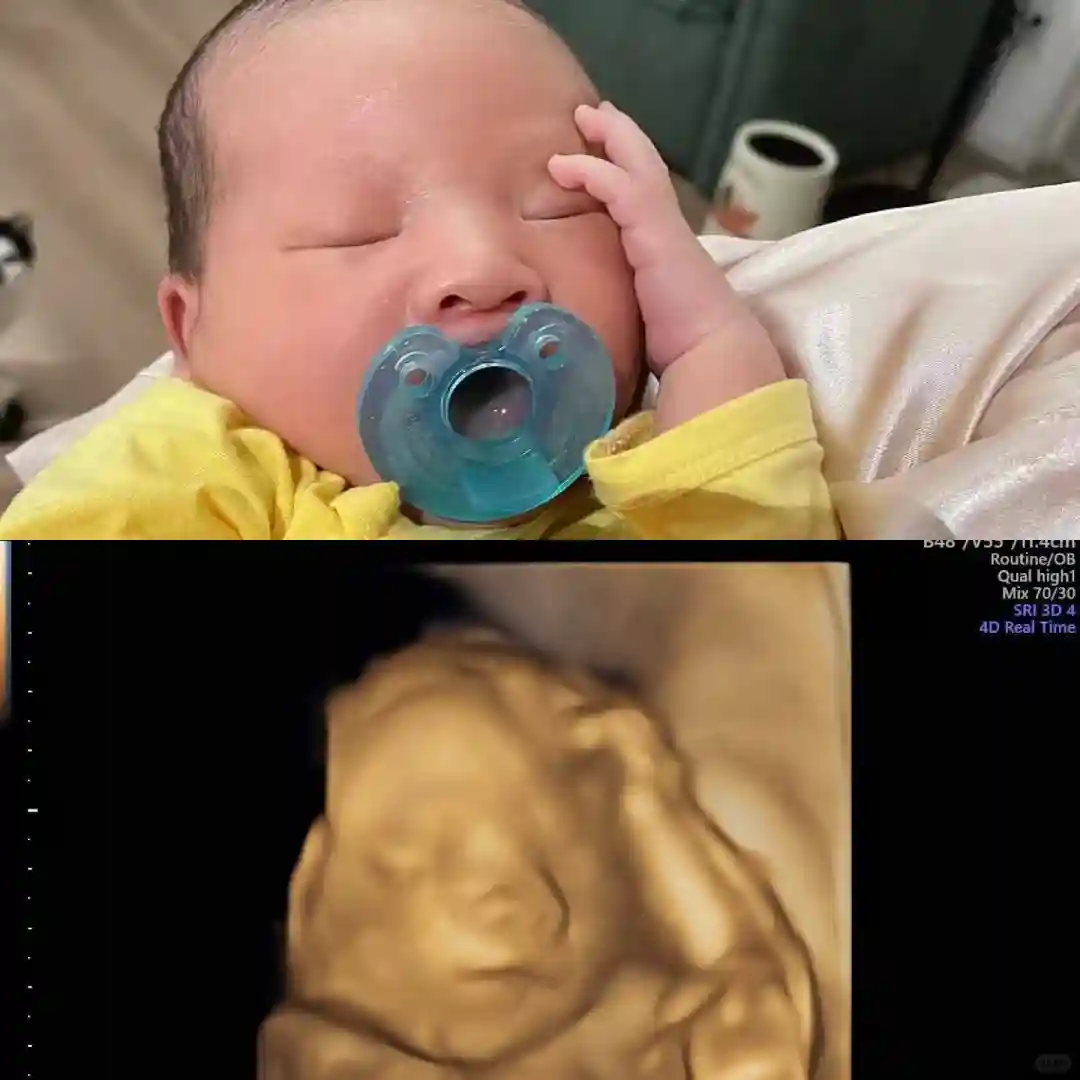

4⃣三/四维超声(20周-26周,24周蕞适宜)‼️三维是照片,四维是照片+视频,做一个就行,有条件的建议直接做四维(杭州的孕期姐妹四维可在省生zhi 中心检查,只要200💰多,其他公立🏥和私立🏥都要1200💰多)。